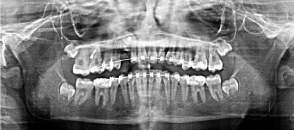

A 12-year-old female came to the dental clinic in the private sector with a chief complaint of unpleasant smile as the upper lateral incisor is flared and missed upper right canine. During our discussion with the patient, her humble request was not to lose any of the permanent teeth. On clinical examination, it’s found that #12 is labially proclined, retained upper right primary canine with slight soft tissue elevation in the labial sulcus on palpation. Intraoral photographs showed misalignment of teeth with shifted upper midline to the right side (Figure 1). A poor oral hygiene had been noticed with a generalized mild upper and lower gingivitis. Panoramic radiograph showed impacted #13 which is overlapping the apical 1/3 of the lateral incisor with retained primary canine (Figure 2). The mesial surface of the canine is passing the root of the lateral and almost flushing with distal surface of the apical third of the central incisor. Periapical radiograph in different horizontal directions (SLOB) techniques along with the palpation and the labial proclination of the lateral incisor confirmed that the impacted canine is labially located. Lateral cephalogram revealed that the incisal edge of the canine is labial to the roots of the incisors. Cephalography analysis documented that patient has skeletal class I malocclusion with decreased anterior facial height and relatively proclined upper and lower incisors. The soft tissue analysis showed that upper and lower lips are relatively behind the Esthetic line (E-line) by 4mm for the upper and 3.6mm for the lower (Table 1).

0.022 slot Roth brackets had been bonded on all upper and lower teeth except #12 which acted as a free body initially till the canine had been moved away from its root (Figure 3). After 6 months of alignment, space started to be created for the canine using opening coil spring (0.010 x 0.035 inch) (Figure 4). The first stage of surgery was planned to be VISTA technique in order to move the canine horizontally and to situate the canine crown directly under its socket using the microimplant (MI) (Figures 5 and 6). During surgery, all the bone distal to the canine crown till its CEJ which is in the way of its movement had been removed. A microimplant from (Ormco) VectorTas of 2 x 8 mm had been placed in the infrazygomatic crest parallel to the upper right first molar (Figure 7). A lingual button bonded on the labial surface of the canine and connected to the microimplant via a power chain which was passing under the alveolar mucosa over the canine. The horizontal movement of the crown had been activated every month by cutting a hole from the power chain. A panoramic periapical radiograph A-B taken directly after MI placement and 3 months over that to control the movement of the canine (Figures 8 and 9). After 3 months of horizontal movement of the canine, the patient referred again for the 2nd stage of surgery where a full reflected flap performed in order to remove the old power chain and place new one which is directly connected to the main archwire (Figure 10). All the bone above the canine crown till the 2 mm from the alveolar crest had been removed in order to facilitate the tooth movement vertically. The main arch wire which is 0.017x0.025 Stst had been offset in the area between #12, 14 (Figure 11). This offset placed to help for keeping the canine root in the alveolar bone and avoid the labial tipping of the crown. A crimpable attachment with a hook fixed on the wire directly over the canine crown and a power chain connected directly from the lingual button to the hook (Figure 12). The vertical movement of the crown had been activated every month by cutting a hole from the power chain. After the canine came out of the soft tissue a bracket bonded and thin wire placed in its slot with a sequence of 0.12 Niti, 0.14 Niti, 0.16 Niti, 0.16 x 0.22 Niti, 0.16 x 0.22 Stst, 0.17 x 0.25 Niti and 0.17 x 0.25 Stst. Canine root torque had been checked after its reaching to the occlusal plane and found that no need for any adjustment since it is similar with the opposing canine root eminence (Figure 13). After 24 months of active treatment, all appliances were debonded (Figure 14). Orthopantogram, lateral cephalography and periapical radiograph had been taken to record as a baseline for future follow up and assessment. Clear overlays delivered for both arches as retainers with proper instructions (Figure 15).

Figure 7. A panoramic radiograph shows the insertion of the micro implant and the button which had been to the labial surface of #13

Figure 8. A panoramic radiograph 3 months past traction #13